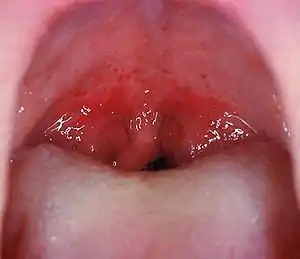

Soft palate without tonsils (after tonsillectomy)